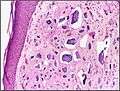

Micrograph of calcinosis cutis. The calcification is purple (bottom of image). H&E stain.

Calcinosis cutis (or cutaneous calcification) is a type of calcinosis wherein calcium deposits form in the skin. A variety of factors can result in this condition. The most common source is dystrophic calcification, which occurs in soft tissue as a response to injury. In addition, calcinosis is seen in Limited Cutaneous Systemic Sclerosis, also known as CREST syndrome (the "C" in CREST). In dogs, calcinosis cutis is found in young, large breed dogs and is thought to occur after a traumatic injury.